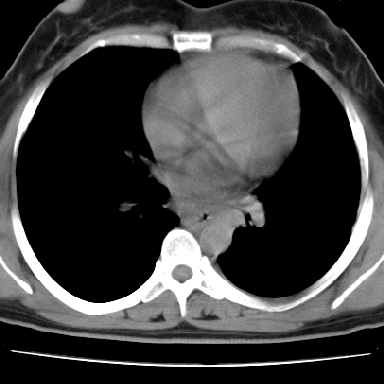

f 37 咳嗽1周,咯血1次,无浓痰,无明显发热

左下肺肿块影,内可以见小泡征,并见厚壁空洞形成,洞内缘可见壁结节。靠近胸膜侧可见胸膜肥厚粘连。双肺可见多发性小结节影。

考虑:左下空洞性肺癌伴两肺转移

偏心性厚壁空洞,壁结节,胸膜肥厚粘连,双肺多发性小结节灶。这么多典型征象,即使错了也错的有道理!

病灶与临床特点:1 位于下肺外围.2 与胸膜关系密切并明显胸膜反应.3 空洞内壁虽见壁结节,但还是较光滑.4 病灶周围明显渗出.5 另肺内多发小结节.6 临床症状轻,发病时间短.综合考虑:肺内特殊感染(霉菌感染).